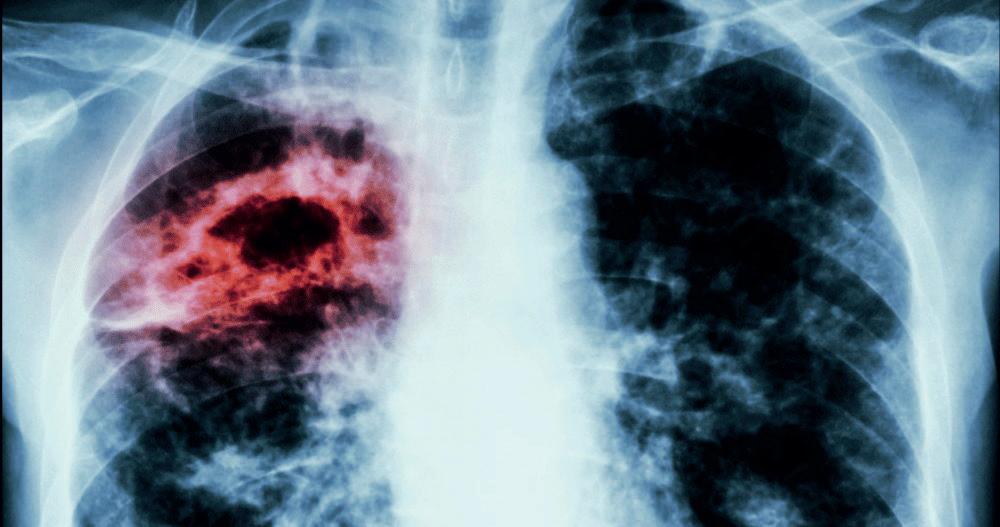

Se registra un repunte de la enfermedad infecciosa con más de 4,000 casos confirmados durante el primer trimestre del 2025

La tuberculosis se posiciona como la segunda enfermedad con mayor prevalencia en México durante el primer trimestre de 2025, sólo por debajo de la influenza, según datos oficiales de la Secretaría de Salud. De acuerdo con el Boletín Epidemiológico, hasta la tercera semana de marzo se han confirmado 4,113 casos de

tuberculosis en todo el país, siendo Baja California (248), Nuevo León (233) y Veracruz (221) las entidades con mayor número de contagios. Tan solo en la semana del 9 al 15 de marzo se reportaron 371 nuevos casos.

Los registros de este año representan ya una séptima parte del total de contagios confirmados durante 2024,

cuando se contabilizaron más de 28,000 casos, aunque estimaciones del Sistema Nacional de Vigilancia Epidemiológica señalan que la cifra real podría superar los 30,000 debido al subregistro.

La tuberculosis, enfermedad infecciosa causada por el Bacilo de Koch, puede afectar distintos órganos

del cuerpo, aunque su manifestación más común es en los pulmones. Se estima que una persona enferma sin tratamiento puede contagiar entre 15 y 20 personas al año.

Este repunte se suma a los brotes actuales de tos ferina y sarampión en el país, lo que ha puesto en alerta a las autoridades sanitarias.

El titular de la Secretaría de Salud, David Kershenobich, anunció que a partir del próximo mes se retomarán las Semanas Nacionales de Vacunación, con el objetivo de reforzar la prevención de enfermedades consideradas erradicadas o bajo control. Una de las preocupaciones centrales es el impacto de la política antivacunas, que ha ganado presencia en diversos países y ha facilitado el resurgimiento de padecimientos prevenibles.